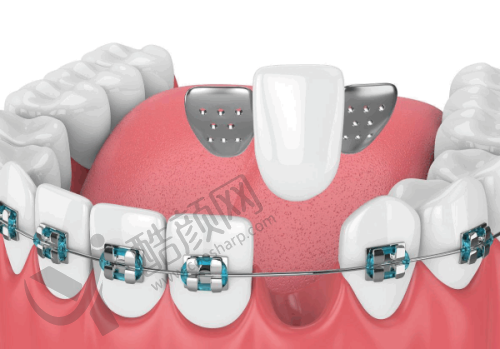

襄阳牙牙口腔是一所集口腔内科治疗、牙齿种植以及牙齿矫正等多项目于一体的欧式口腔诊疗机构。目前医院开设牙齿美容中 心、牙齿矫正中 心以及活力儿童齿科等六大特色诊疗科室。具体项目包括镶牙、种植牙、牙齿美白、牙体牙髓治疗、牙周病治疗、牙齿矫正及儿童牙科等。无论是日常的口腔护理,还是复杂的牙科手术,在这里都能得到专精的治疗。

医院借鉴了来自于美国以及德国的成熟口腔检查模式,还吸取了来自于韩国精良的口腔医疗管理经验,在医疗技术的引进方面以及医疗设备的引进等多个方面实现了合作与共享。在设备上,引进了多种精良设备。CBCT机以其三维成像技术,能够清晰地展示口腔结构,帮助医生进行更正确的诊断和治疗规划。全景机则提供了广泛的视野,使得牙科医生可以全方面评估患者的口腔健康状况。超声洁治器利用高频声波技术,能够有效去除牙结石和牙菌斑,降低患者的不适感,提升洁治成效。根管测量仪确保根管治疗的正确度,帮助医生正确测量根管长度,避免治疗中的潜在风险。根管填充器则能够效率高且均匀地填充根管,确保治疗的成功几率。激光设备在口腔治疗中具备舒适、快速的优势,能够有效促进创口愈合,减少术后并发症。